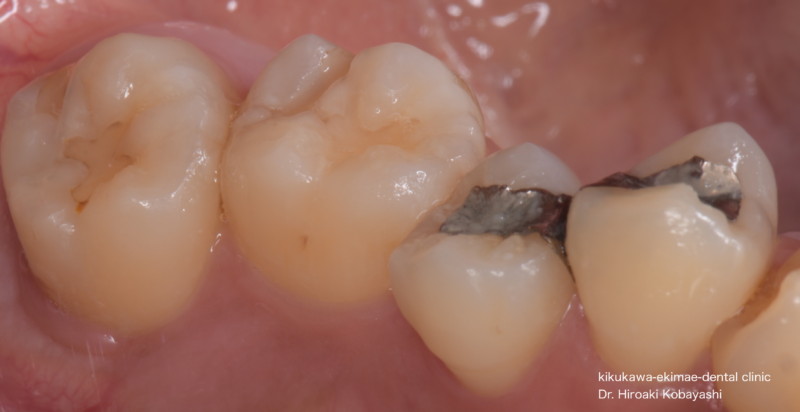

部位が特定できない歯のお痛みのご相談でした。レントゲン上にて一番奥歯の歯の神経の炎症が原因と疑われましたが、他院にて最近,保険の樹脂を詰めたので後から行いたいというご希望と、侵襲が少ない箇所からの治療をご希望されましたので2次感染が起きている銀歯や保険の白い樹脂が詰まっている箇所から治療を開始しました。

手術用顕微鏡下にて虫歯を取りきり、接着処理を確実に行います。虫歯治療において歯の予後を考える上でここが一番大事なステップになります。保険の処置では唾液の侵入などを考慮し接着操作は20秒ぐらいで終わらせざるおえないステップですが、接着処理は確実に行うとすると少なくとも5分以上かかる処理になります。

手術用顕微鏡下にて精密根管治療を行います。根の中は複雑な形をしており、途中から根が繋がり、感染物質を除去する際の死角となっていたり、根の中に石灰化物が存在し、根の先を塞いでいたりしていたりなど、様々な要因が治癒の妨げになります。